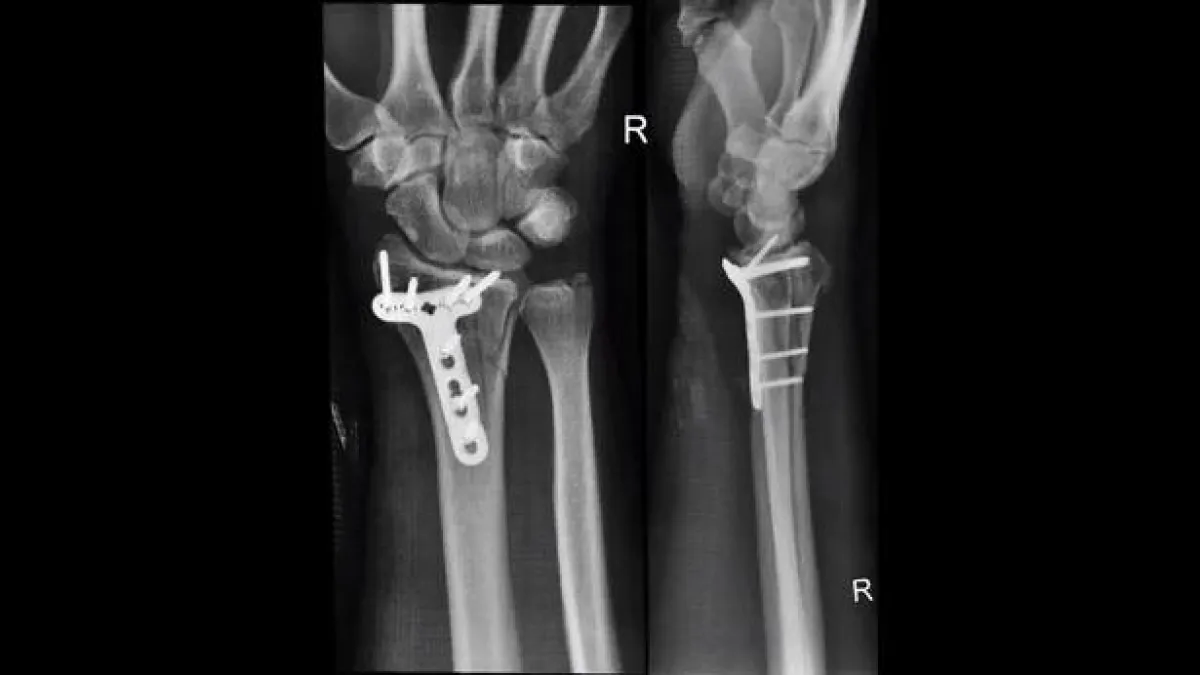

هبط الطيار بأمان في وقت لاحق وتم نقل «كريس» إلى مستشفى محلي، حيث كانت هناك حاجة إلى لوحة من التيتانيوم وسبعة مسامير لإصلاح معصمه المكسور أثناء الجراحة.

«كريس» في تجربته القريبة من الموت في اليوم الأول من رحلته إلى سويسرا، أصيب بكسر في الرسغ وتمزق في عضلة الفخذ، ولكن النتيجة كان يمكن أن تكون أسوأ بكثير.